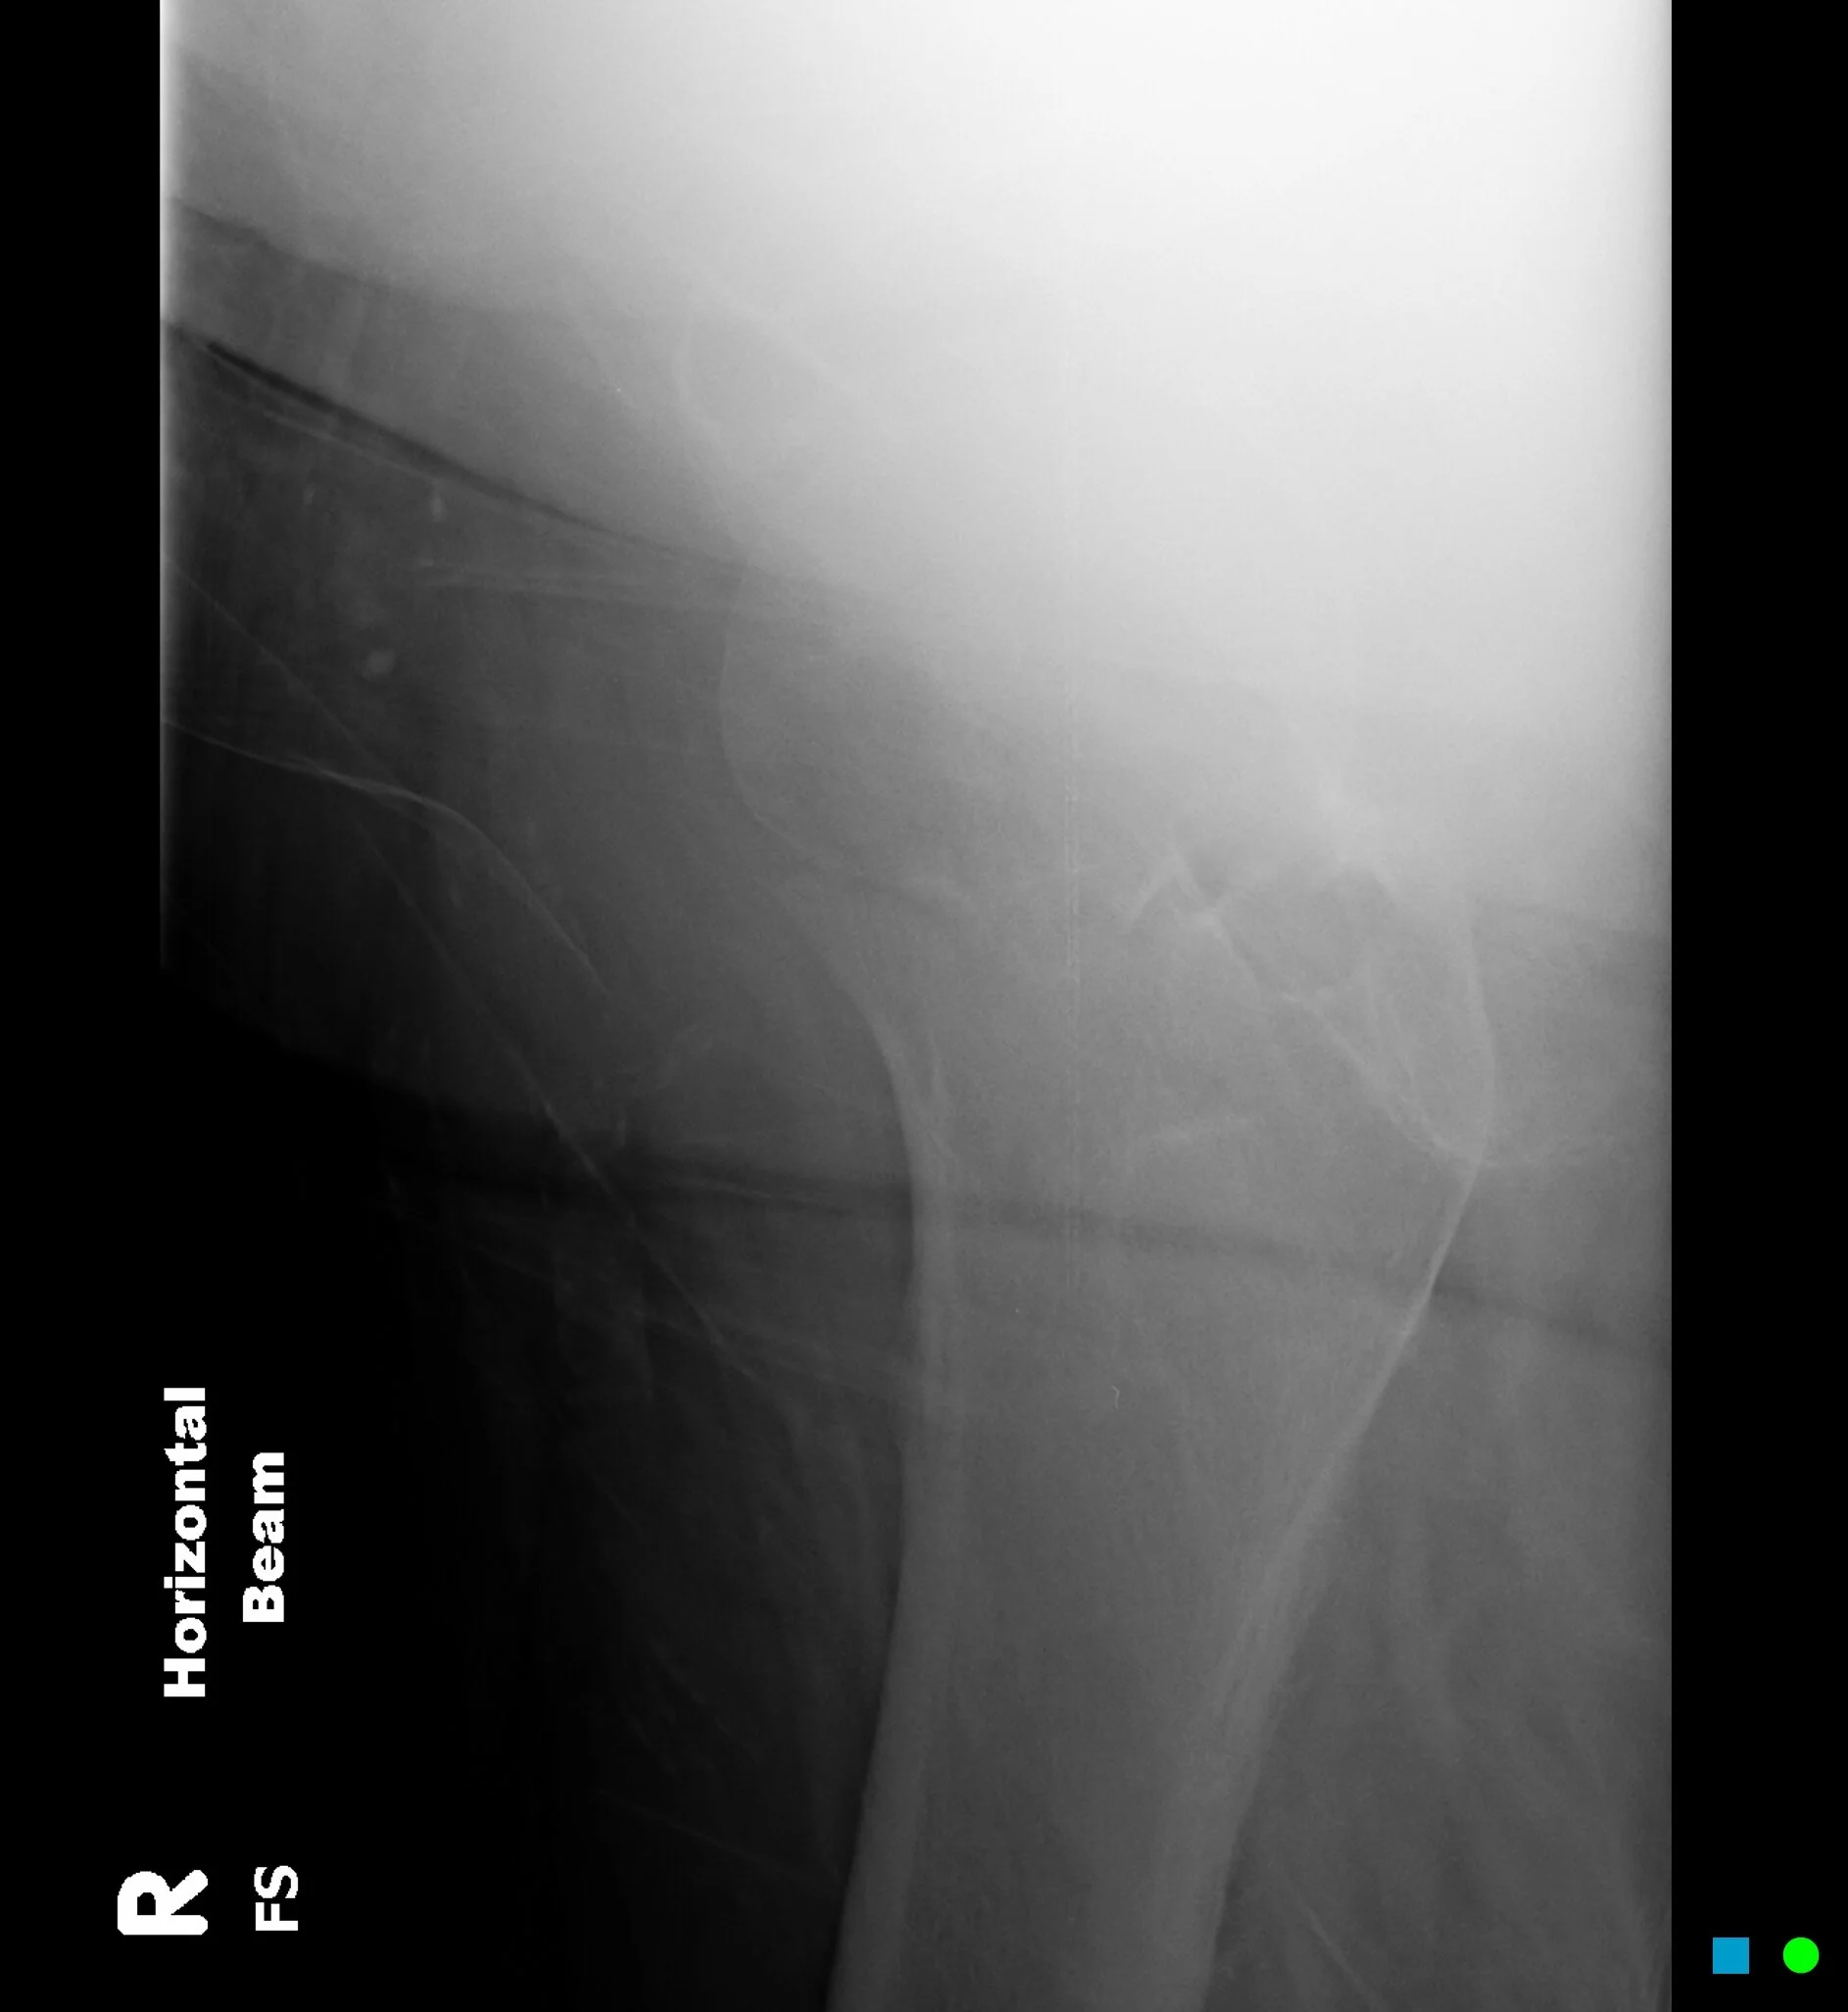

The following is a hip x-ray of a 90yo male who presents to the ED.

Lateral

Fractured right neck of femur

According to the garden classification, what type/stage is shown in the above images?

Garden Type III: complete fracture, incompletely displaced. For more info: https://radiopaedia.org/cases/garden-classification-of-hip-fractures-diagram?lang=gb